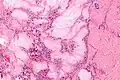

A tophus (Latin: "stone", plural tophi) is a deposit of monosodium urate crystals, in people with longstanding high levels of uric acid (urate) in the blood, a condition known as hyperuricemia. Tophi are pathognomonic for the disease gout. Most people with tophi have had previous attacks of acute arthritis, eventually leading to the formation of tophi. Chronic tophaceous gout is known as Harrison Syndrome.[1]

It appears that monosodium urate crystals trigger a distinct physiological NETosis pathway that coats them in DNA. These coated crystals then persist in tissues as a foreign body granuloma constituting gouty tophus.[4]